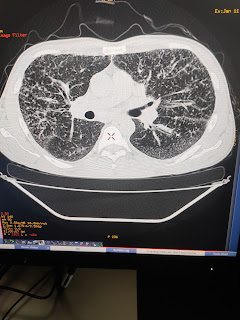

Middle lobe consolidation with bronchiectasis

PA view of chest x ray show dense lesion silhouetting medial border of heart with ovious outline of right dome of diaphragm indicating involvement of middle lobe ( which is ovious in lateral chest x ray .

What are possible causes ?

TB

Non tuberculosis mycobacteria

Ciliary dyskinesis